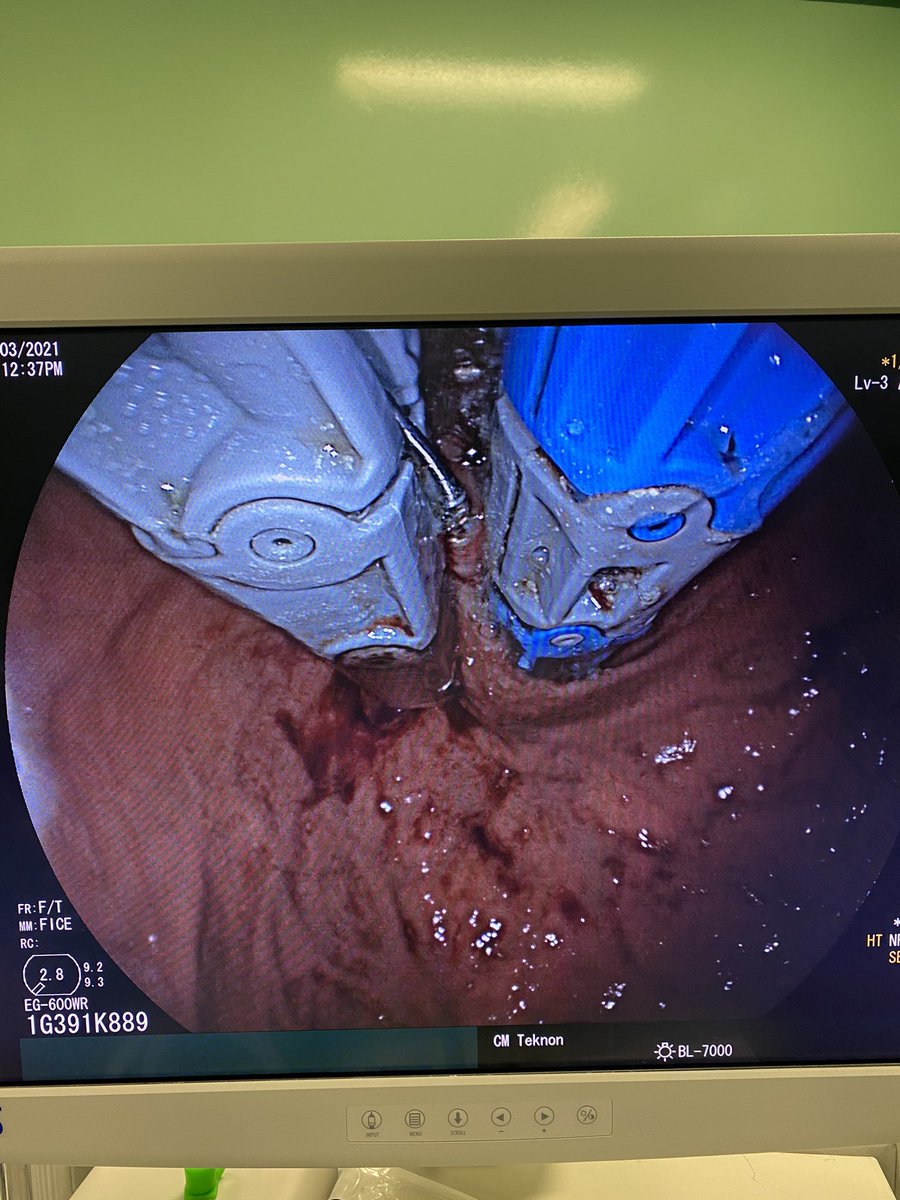

Sequence of first bite for a #Rose procedure for reparation of #bypass #RNY of 5 cm pouch with an anastomosis over 25 mm. We used the 33 mm @USGIMedical #Gprox avoiding the #APC due the lack of space #bariatricendoscopy @sa6ater @MetabolicEndo @SighPichamol thoughts?

2nd and 3rd bites. Less than 10 minutes procedure. Safe, clean and effective. @Clinica_Teknon #bariatricendoscopy #bypassreparation #ROSEprocedure #obesidad #endoscopia @EEndoscopia @TerapiasObesid